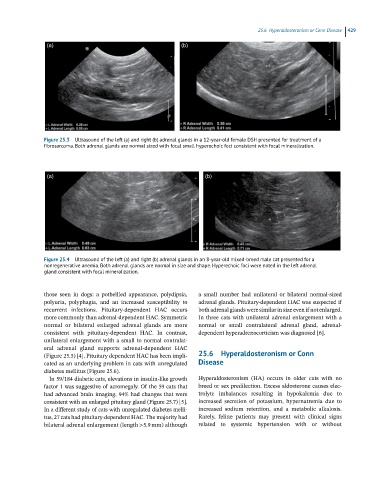

Figure 25.4 Ultrasound of the left (a) and right (b) adrenal glands in an 8-year-old mixed-breed male cat presented for a

nonregenerative anemia. Both adrenal glands are normal in size and shape. Hyperechoic foci were noted in the left adrenal

gland consistent with focal mineralization.